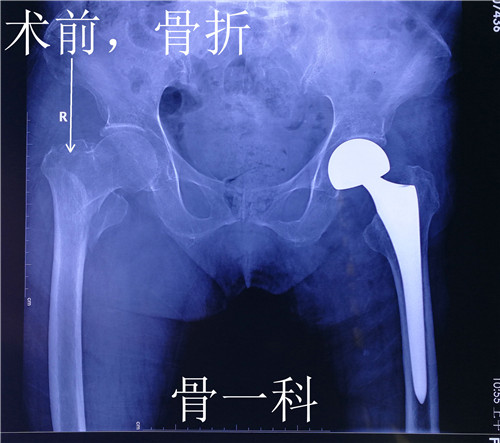

据了解,来自渭南市临渭区的郑老太太,年近92岁。9个月前因外伤导致左股骨颈骨折,骨一科为她实施了左侧人工股骨头置换术,术后老人恢复良好,一直在西安女儿家生活。这次老人散步时又不慎摔伤,当即感觉右髋部疼痛,无法站立行走,随后亲属将她送到就近的西安一家医院就诊。在医院拍右髋部x线检查显示,老人右股骨粗隆间骨折粉碎性骨折。该院让她住院手术治疗,她坚决要回渭南在骨一科治疗。

骨一科翁主任和全科医生对老人病情进行了评估和讨论,由于老人是高龄患者,除了右侧股骨粗隆间骨折,之前左侧还做过人工股骨头置换术,并且有骨质疏松症、高血压病、糖尿病Ⅱ型,手术风险和麻醉风险都特别大。在麻醉科李万鹏副主任和徐巧玲主任医师的协助下,骨一科为老人实施了右股骨骨折闭合复位髓内针内固定术,手术非常成功。此手术面对老年髋部股骨粗隆间骨折的特殊人群,优点是减少出血、缩短手术时间、减少创伤、减少麻醉时间,极大降低手术风险。